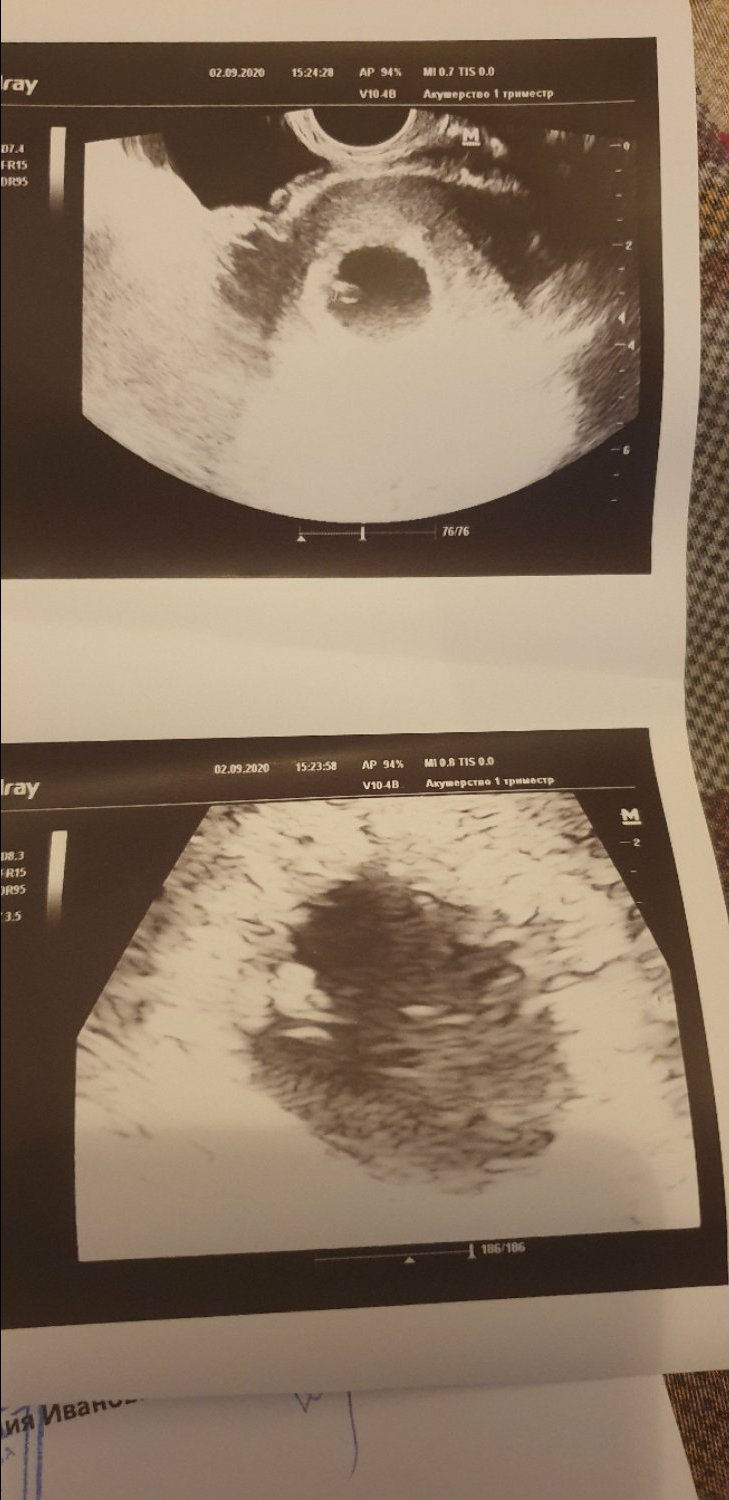

Всем привет! Сегодня сделала УЗИ, и увидела крошечное счастье. Дай бог здоровья нам😇😍🥰

Дай Бог вам здоровья 🥰 Помню, какое это счастье, УЗИ, на котором сердечко определили. У вас видимо хорошее УЗИ попалось. У меня на вашем сроке ещё эмбрион не разглядели. Только на 7 неделе.